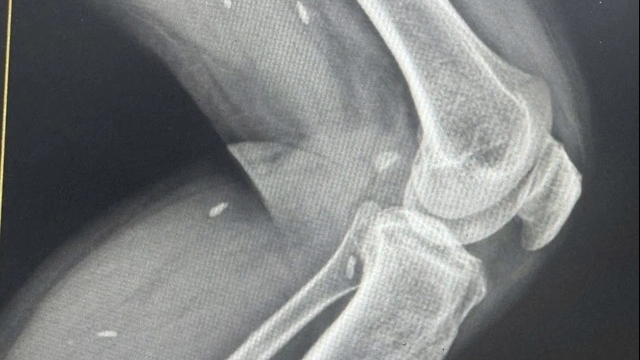

Tương tự, bệnh nhi thứ hai nhập viện cũng 3 tuổi, bị trâu nhà hàng xóm húc vào đầu trong lúc bé chạy đuổi theo trâu. Sau khi bị trâu húc, bé bị chảy nhiều máu và được gia đình đưa đi bệnh viện tuyến tỉnh cấp cứu.

Tại cơ sở y tế này ghi nhận bé bị lõm xương sọ và một phần tổ chức não bị lộ ra ngoài. Ngay lập tức trẻ được chuyển đến Bệnh viện Nhi Trung ương trong đêm 18/1.

Các bác sĩ bệnh viện Nhi Trung ương xác định trẻ bị vết thương sọ não do trâu húc, được băng cầm máu và làm các xét nghiệm cấp, chuyển bệnh nhi phẫu thuật ngay sau khi bệnh nhi nhập viện khoảng 3 giờ đồng hồ.